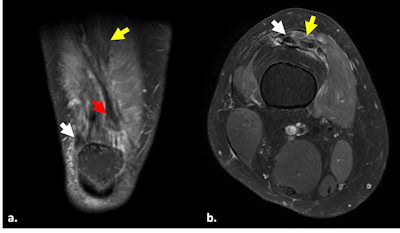

Quadriceps tendon rupture. Fat-suppressed proton density-weighted coronal (a) and axial (b) images show complete rupture of the conjoined portion of the vastus medialis and lateralis tendons of the quadriceps at its medial margin, with torn end retracted 2 cm (red arrow). Lateral insertion into the patella is preserved (white arrows). Complete rupture of the intermediate vastus (yellow arrow).